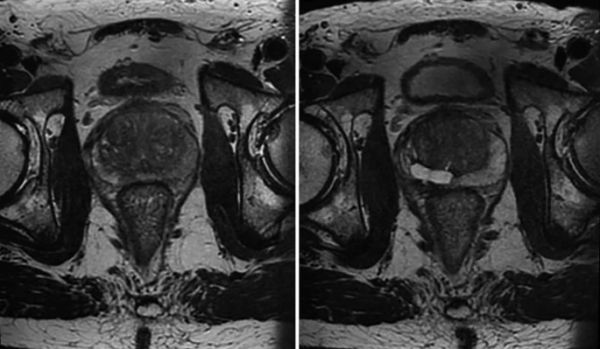

用于前列腺癌的 IRE 具有良好的耐受性,并且在手术前后的泌尿、肠道、身体和精神评分方面具有可比性。这与前列腺段消融无关 [ 20 , 21 ]。冈瑟等人。报告了超过 471 名患者接受局灶性局部疾病或高风险或抢救治疗的结果。没有观察到尿失禁,性功能下降是一种短暂的影响,12 个月后只有 3% 的残余勃起功能障碍。已经确定了基线时的性功能、患者年龄和结果之间的关系。最低的术前性状态对应于性保存方面较差的结果 [ 15 , 22 ]。 通过 PSA、影像学和再活检评估前列腺 IRE 的肿瘤学结果。对局灶性/偏侧切除术和全腺体切除术的最大回顾性研究发现 6 年的无复发生存率为 90%,这使得 IRE 与根治性前列腺切除术的结果相当 [ 15 ]。 成像最好通过对比增强超声或 MRI 进行,与前列腺切除标本相比,这两种技术都可以可靠地估计消融体积和位置 [ 23 ](图 16.6 和 16.7 )。 图 16.6

IRE 前(左)和 6 周后(右)前列腺右后叶的 MRI 图像。MRI 显示在目标体积部位充满液体的空腔。T2 加权图像 图 16.7